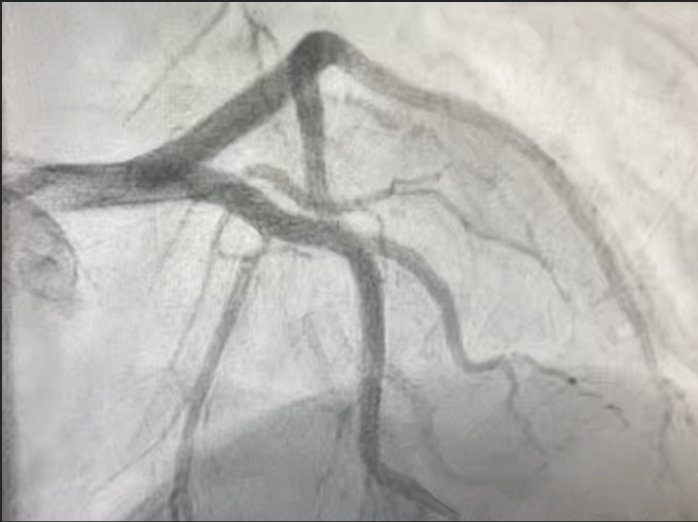

Cardiac Catheterization Findings

- Dissection of the left anterior descending (LAD) artery extending beyond the takeoff of the principal diagonal branch;

- Total occlusion of the apical LAD, likely due to distal embolization;

- Two drug-eluting stents were successfully deployed to restore flow.

SCAD angiographically presents with hallmark features including intramural hematoma, with or without an intimal tear, and typically involves the LAD artery.1,3 In our case, the LAD dissection was confirmed and treated with PCI. While conservative management is generally favored due to the high spontaneous healing rates, PCI is indicated in high-risk cases with ongoing ischemia or hemodynamic instability, as in our patient.1,2,3